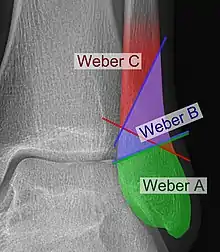

The Danis–Weber classification (often known just as the Weber classification) is a method of describing ankle fractures. It has three categories:[1]

- Type A

Fracture of the lateral malleolus distal to the syndesmosis (the connection between the distal ends of the tibia and fibula). Typical features:

- Type B

Fracture of the fibula at the level of the syndesmosis. Typical features:

- Type C

Fracture of the fibula proximal to the syndesmosis. Typical features:

Categories B and C imply a degree of damage to the syndesmosis itself (which cannot be directly visualised on X-ray). They are inherently unstable and are more likely to require operative repair to achieve a good outcome. Type A fractures are usually stable and can be managed with simple measures, such as a plaster of paris cast.